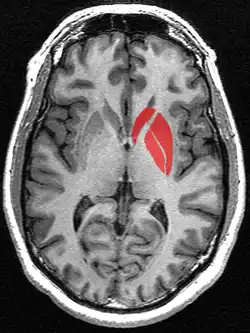

Striatum highlighted in green on coronal T1 MRI images -

Striatum highlighted in green on sagittal T1 MRI images -

Striatum highlighted in green on transversal T1 MRI images